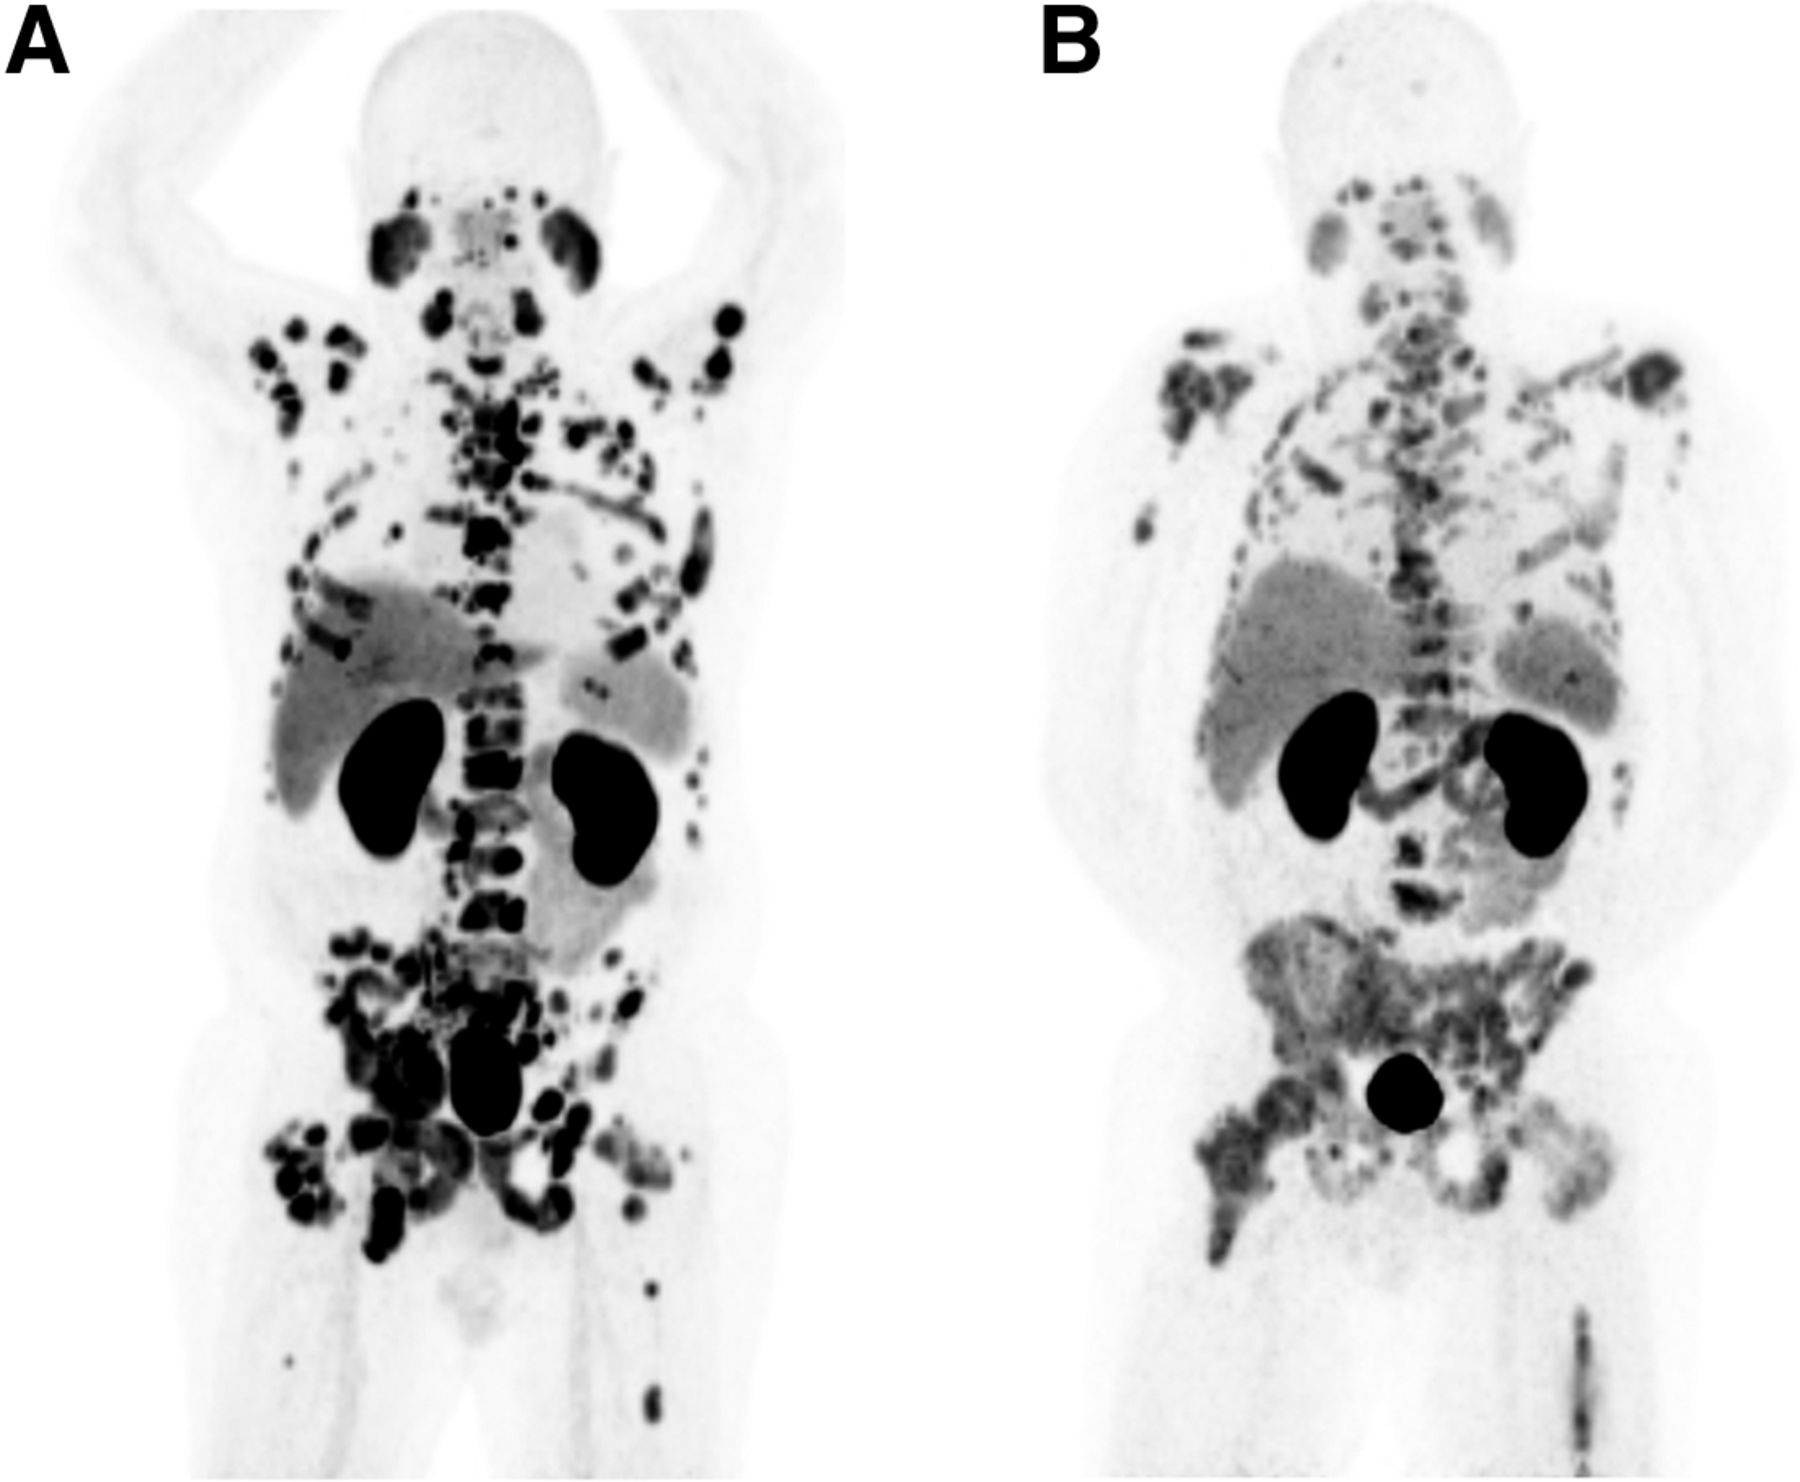

La Administración de Alimentos y Medicamentos de los Estados Unidos (FDA) ha aprobado los agentes dirigidos al antígeno de membrana específico de la próstata (PSMA), 68 Ga-PSMA-11, 18 F-DCFPyL y 18 F-rhPSMA-7.3, para la obtención de imágenes PET (PSMA PET) para múltiples indicaciones. Las directrices actuales recomiendan específicamente la PSMA PET con esos radiotrazadores en pacientes con CP y metástasis sospechadas que son candidatos para la terapia definitiva inicial y que tienen una recurrencia sospechada basada en un nivel elevado de antígeno prostático específico (PSA) para determinar la elegibilidad para el tratamiento con terapia radiofarmacéutica dirigida a PSMA, como 177 Lu-PSMA-617 . La PSMA PET ha demostrado una mayor precisión de detección en el CP en comparación con la obtención de imágenes convencionales; sin embargo, su superioridad para fines de evaluación de la respuesta al tratamiento no se ha establecido según nuestro conocimiento. Se han desarrollado métodos de evaluación de respuesta para PSMA PET que distinguen respuesta parcial (RP), respuesta completa (RC), enfermedad progresiva (EP) o enfermedad estable (ES) . Está surgiendo evidencia con respecto al valor pronóstico de la categorización de respuesta de enfermedad metastásica usando PSMA PET en pacientes con CP que están siendo tratados con inhibidores de la vía del receptor de andrógenos (IPRA), taxano o terapia con radiofármaco 177 Lu-PSMA. Las guías de diagnóstico por imagen recientes recomiendan que se realice una PET PSMA basal antes del inicio de terapias sistémicas, y se debe realizar una PET PSMA de seguimiento cuando se espera que los resultados cambien el manejo clínico. Se debe realizar una exploración de fin de tratamiento al menos 3 meses después de que el tratamiento sistémico haya concluido.

Un tema importante que se analiza con más detalle en este artículo es el fenómeno de brote postulado causado por el aumento de la expresión de PSMA tras el inicio de la terapia de privación androgénica (TPA) o ARPI en la población resistente a la castración, mientras que en la enfermedad hormonosensible, podría haber una disminución de la captación, lo que podría subestimar la carga de la enfermedad. Se necesitan más estudios para esclarecer por completo el papel de la PET con PSMA en la evaluación de la respuesta durante la terapia hormonal en el cáncer de próstata.